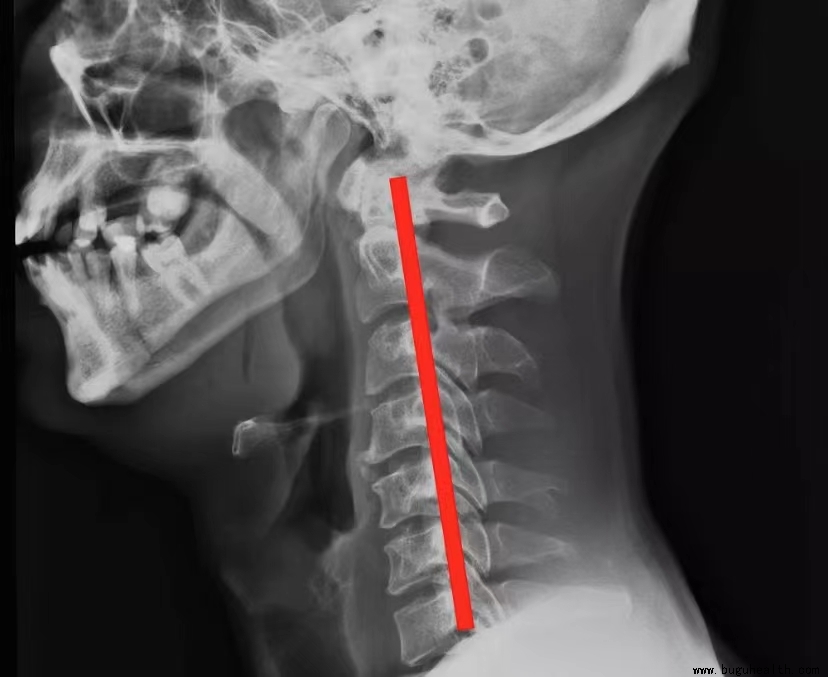

颈椎曲度变直,是现代人常见的健康问题之一,主要由于长时间不良坐姿、缺乏运动等因素导致。这种变化不仅影响颈椎的正常生理功能,还可能引发一系列颈部不适和疼痛。

颈椎在正常情况下,有一个向前凸的生理曲度,它能够有效地维持颈椎的正常生理功能,增加颈椎弹性,减轻重力震荡。当这个生理曲度消失,甚至反弓时,就会出现颈椎曲度变直的情况。这不仅会导致颈椎的稳定性下降,还会对脊髓和大脑造成潜在损伤。